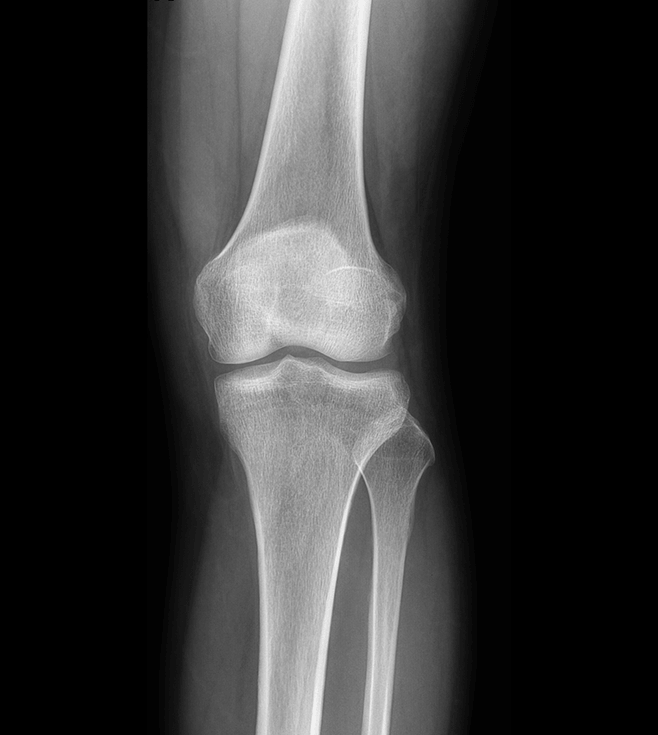

多功能诊断专用动态DR

太阳成集团tyc122cc入口科技全新设计的第四代床式动态DR,集拍片、透视、造影、全身拼接、尘肺体检于一体,一机多能,真正意义上实现全科室应用,提升医院实际效益。

多功能诊断应用专业设计

从医疗机构放射科的实际应用出发,针对多功能诊断进行多维度专业设计,优化病人检查体验,大幅提升操作技师工作效率。

高清动态平板探测器

搭载自主研发超清大视野动态平板探测器,600微米碘化铯大幅提升X线转化效率,独特的非晶硅阵列与高速读取集成电路紧密协作,轻松实现多帧率透视与高清点片。

专业的影像处理系统

“腾灵”系列搭载的IEAE影像处理系统,具备多项发明专利。本系统采用多频域图像处理技术,其6大核心处理模块使影像具有优秀的一致性、柔和性、空间层次感和纹理细腻度,为用户精准诊断病灶奠定了坚实的基础。